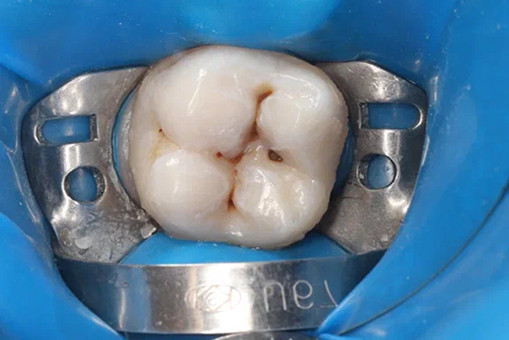

Лечение кариеса проводится следующим образом - сбор анамнеза, проведение местной анестезии, дентальный снимок (при необходимости), изоляция (коффердам), фотопротокол, удаление кариозных тканей (с использованием бора), антисептическая обработка полости, реставрация пломбировочным материалом, шлифовка, полировка.

До/после лечения